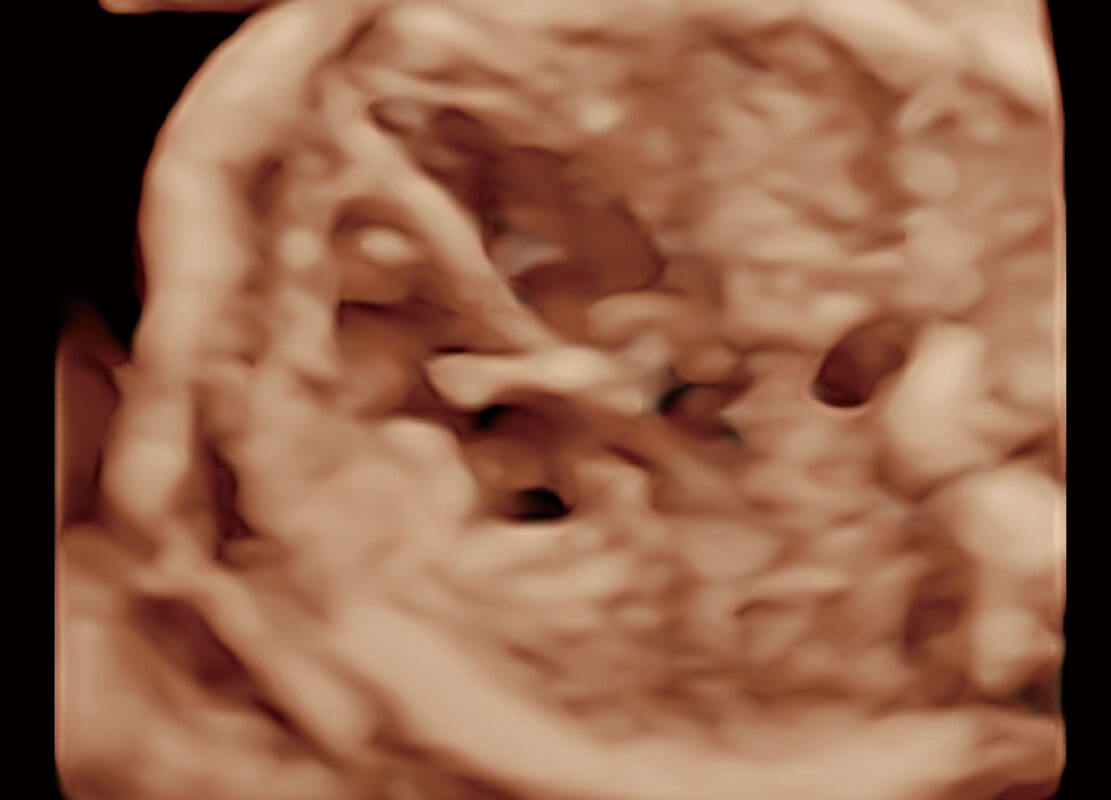

高分辨率容积成像-早孕胎儿

胎儿体循环

光影成像-孕囊